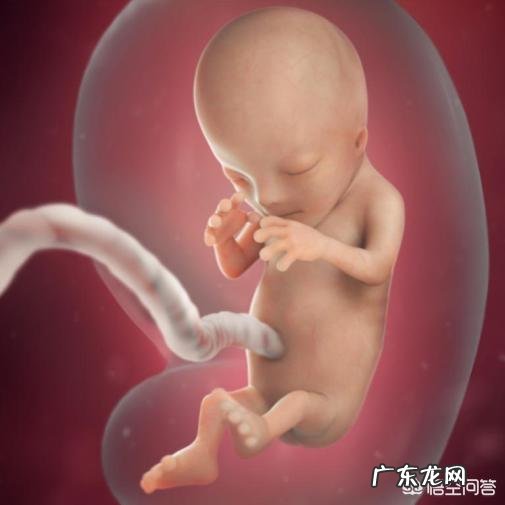

怀孕到38周,此时胎宝宝身长约47.5cm,胎重约3000g,双顶径平均值9.08±0.59cm,腹围平均值30.63±2.83cm,股骨长7.20±0.43cm 。胎宝宝的身体还在继续生长,脂肪的储备有助于出生后调节体温,覆盖在身上的那层绒毛和白色的胎脂逐渐脱落,皮肤皱纹逐渐消失,皮肤变得光滑起来 。

此时孕妈妈的体重增加了12kg左右,手脚非常肿胀,下腹部的压力越来越大,大部分的胎儿已经入盆,大肚子往下坠,肺部和胃部的压力减轻了些,孕妈妈会感觉呼吸和进食顺畅了许多 。

怀孕到38周,宫内环境几近成熟,临产的征兆随时可能发生,不要远门,家人要陪同在身边 。

子宫内空间越来越小,胎宝宝胎动的频率和强度都减弱了,但不意味着没有反应,孕妈妈要记录胎动次数,如果子宫没有出现规律性收缩,就出现了羊水破裂的症状,孕妈妈一定要立即去医院 。